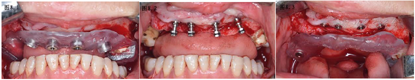

正颌术后半年颌骨愈合良好,上下颌骨骨性反he(牙合)得到纠正,术后影像学显示右侧上颌窦嵴距骨高度不足,17牙临床牙冠伸长且伴松动,前牙区骨量充足,但缺牙区前庭沟变浅伴有角化黏膜量缺损。为减小手术创伤、缩短治疗周期并能够达到长期稳定的治疗效果,设计在前牙区倾斜植入带有光滑颈圈的拓美超亲水种植体,根据植入位点设计并制作2副牙支持式种植手术导板。局部浸润麻醉,牙槽顶黏骨膜切口,翻瓣显露牙槽嵴顶,戴入双侧后牙支持的第一副前牙区种植手术导板(图8.1),逐级备孔,前牙区植入4颗ø4.0*8 mm拓美种植体,初期稳定性均>30Ncm(图8.2)。拔除17、18患牙,戴入左侧后牙支持的第二副种植手术导板(图8.3),17牙位点逐级备孔并植入1颗ø5.0*12 mm拓美种植体,初期稳定性20Ncm,跳跃间隙内植入自体骨屑,所有种植体均埋入式愈合,对位缝合黏骨膜。